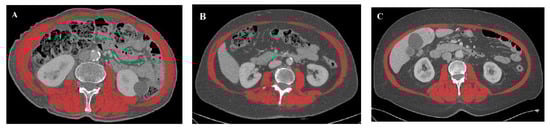

2.2. Image Analysis